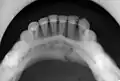

occlusal radiograph of a mandibular parasymphysis fracture